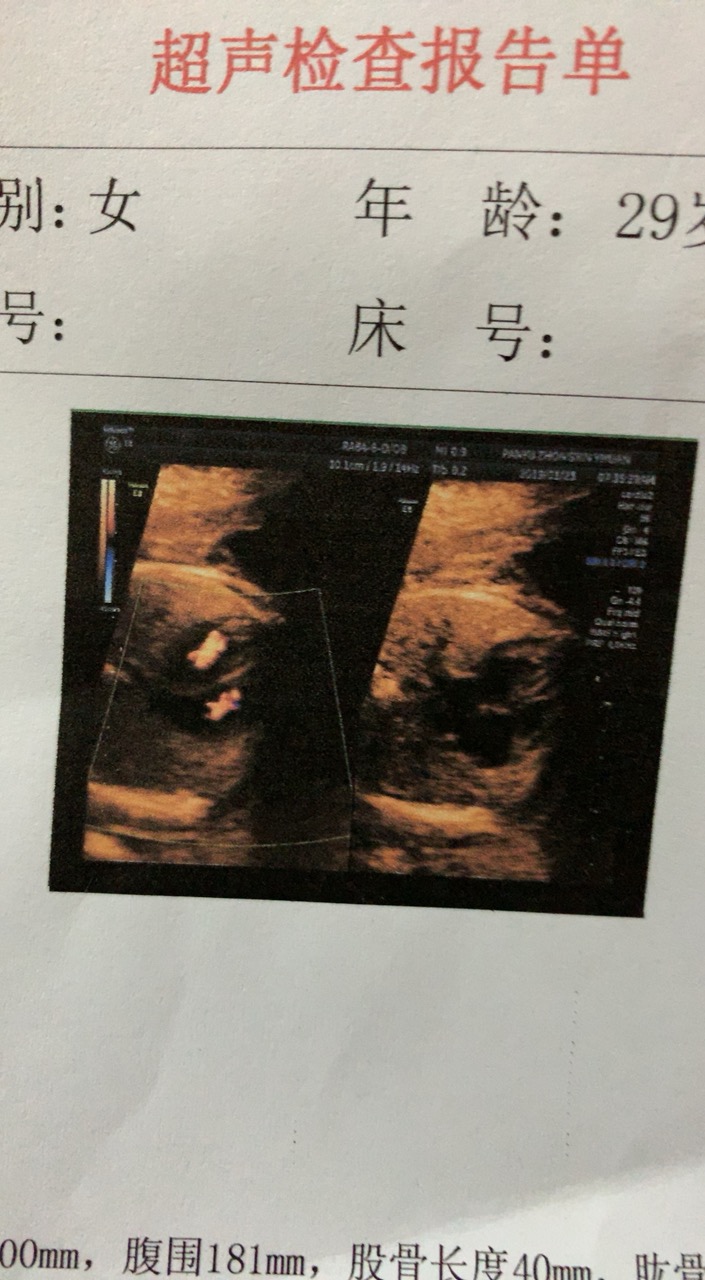

备孕中

孕24周+0天

股骨长4cm了都

看着是啊,两个小人儿样,恭喜